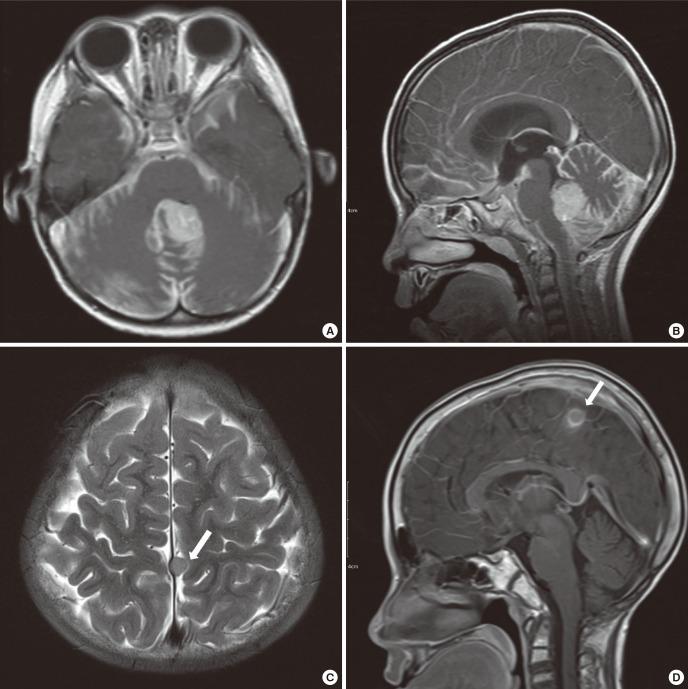

Radiotherapy is one of the standard treatments for medulloblastoma. However, therapeutic central nervous system irradiation in children may carry delayed side effects, such as radiation-induced tumor and vasculopathy. Here, we report the first case of coexisting meningioma and moyamoya syndrome, presenting 10 years after radiotherapy for medulloblastoma. A 13-year-old boy presented with an enhancing mass at the cerebral falx on magnetic resonance imaging (MRI) after surgery, radiotherapy (30.6 Gy craniospinal axis, 19.8 Gy posterior fossa) and chemotherapy against medulloblastoma 10 years ago, previously. The second tumor was meningioma. On postoperative day 5, he complained of right-sided motor weakness, motor dysphasia, dysarthria, and dysphagia. MRI revealed acute cerebral infarction in the left frontal lobe and both basal ganglia. MR and cerebral angiography confirmed underlying moyamoya syndrome. Four months after the meningioma surgery, the patient presented with headaches, dysarthria, and dizziness. Indirect bypass surgery was performed. He has been free from headaches since one month after the surgery. For patients who received radiotherapy for medulloblastoma at a young age, clinicians should consider the possibility of the coexistence of several complications. Careful follow up for development of secondary tumor and delayed vasculopathy is required.

放射治疗是髓母细胞瘤的标准治疗方法之一。然而,儿童中枢神经系统放射治疗可能会带来延迟性副作用,如放射性肿瘤和血管病变。在此,我们报告首例在髓母细胞瘤放疗10年后同时出现脑膜瘤和烟雾病综合征的病例。一名13岁男孩10年前曾接受髓母细胞瘤手术、放疗(全脑全脊髓轴30.6 Gy,后颅窝19.8 Gy)及化疗,此次磁共振成像(MRI)检查发现大脑镰处有一强化肿块。第二个肿瘤为脑膜瘤。术后第5天,他出现右侧肢体运动无力、运动性失语、构音障碍和吞咽困难。MRI显示左侧额叶及双侧基底节区急性脑梗死。磁共振血管造影和脑血管造影证实存在潜在的烟雾病综合征。脑膜瘤手术后4个月,患者出现头痛、构音障碍和头晕。遂进行了间接搭桥手术。术后1个月起患者头痛症状消失。对于幼年接受髓母细胞瘤放疗的患者,临床医生应考虑多种并发症并存的可能性。需要对继发性肿瘤和延迟性血管病变的发生进行密切随访。